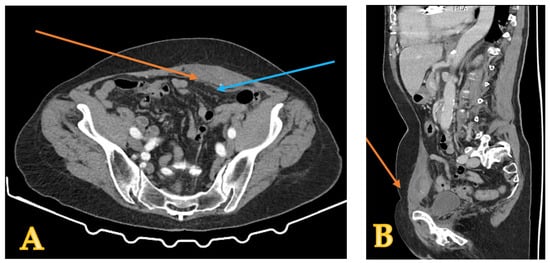

2. Case Presentation